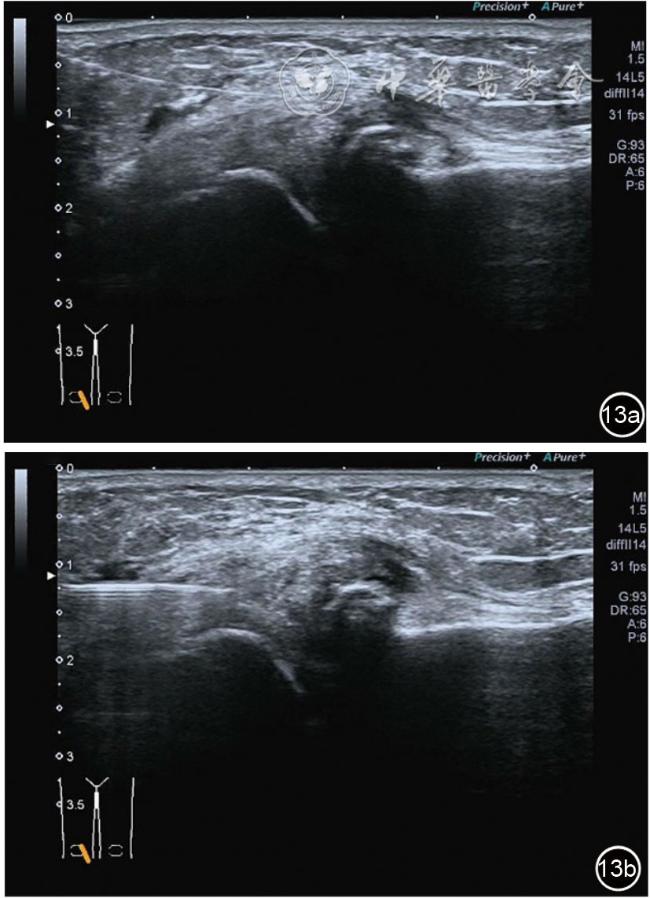

4.神经卡压液压松解加药物注射治疗。膝关节神经卡压主要涉及膝内上支、膝外上支、膝内下支、髌下支。可根据神经支配区域的临床检查确定卡压神经。临床上隐神经髌下支卡压常见。隐神经髌下支从隐神经发出后穿缝匠肌至膝内前下方,与深筋膜紧密相连(图24)。隐神经髌下支卡压出现膝关节内下侧酸痛、麻木,胫骨内侧髁压痛阳性,Tinel征阳性,局部皮肤痛觉减退。确定诊断后可行隐神经髌下支液压松解。患者平卧位,膝关节屈曲30°,下面垫一软枕。一般选用10 MHz以上超声探头,穿刺区域常规消毒,探头涂抹耦合剂后套入无菌手套碘伏消毒或使用无菌耦合剂。首先扫查神经短轴切面,确定神经后旋转为长轴切面引导注射。选用25G穿刺针头,抽吸0.5%利多卡因4 ml+地塞米松3 mg,从近端穿刺,沿神经表面纵轴方向,确定针尖在神经膜外后推注药物进行松解,注射完毕后拔出针头(图25),局部压迫2分钟,创可贴覆盖。

图25 超声引导下隐神经髌下支卡压液压松解加药物注射治疗